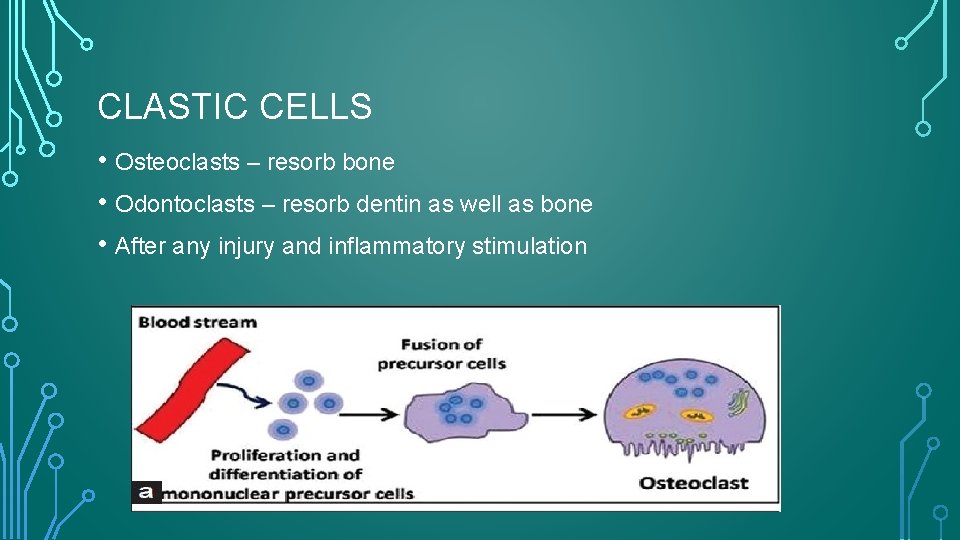

CLASTIC CELLS • Osteoclasts – resorb bone • Odontoclasts – resorb dentin as well as bone • After any injury and inflammatory stimulation